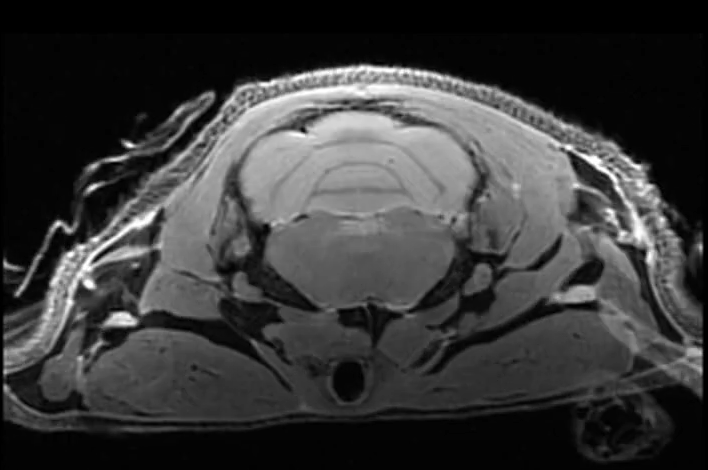

Exemples d'images acquises par notre IRM 7T

IRM d'une colonne vertebrale d'un rat